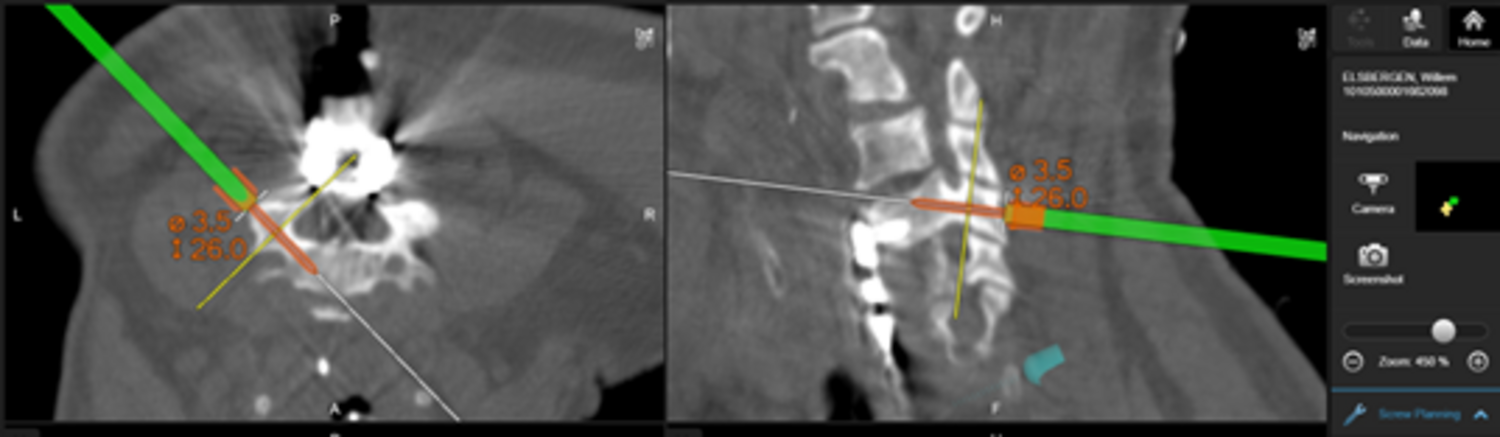

- CT-navigierte (AIRO©) Implantationen:

Seit 2017 führen wir unsere Stabilisierungs- und Versteifungsoperationen mit einem intraoperativen CT (s.o. AIRO©, Fa. Brainlab) durch. Diese intraoperative Computertomographie liefert direkt im Operationssaal während des Eingriffs hochauflösende Bilder von der Wirbelsäule. Zusammen mit einer Navigationssoftware wird ein dreidimensionaler Plan der entsprechenden Körperregion erzeugt. Mit Hilfe der Bildgebung können wir die notwendigen OP-Schritte plangerecht umsetzen und z.B. Implantate mit sehr hoher Präzision einsetzen. Gerade bei komplizierten Eingriffen an der Wirbelsäule hilft die neue OP-Technik, Patienten sicher und schonend zu therapieren. Die intraoperative Bildgebung, direkt im OP, erlaubt komplexe Operationen genauer und sicherer durchzuführen und dem Operateur noch während der Operation das Ergebnis zu überprüfen und bei Bedarf zu optimieren. Belastende Folgeoperationen sind so deutlich seltener und die Behandlungsqualität und Sicherheit für Patienten dadurch erheblich verbessert.